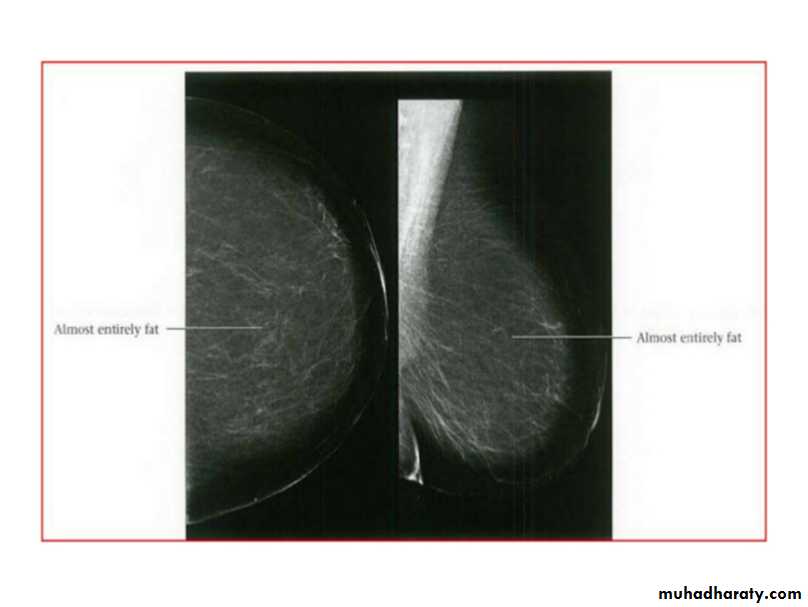

Breast density & who can U detect a mass lesionYour mammogram report must take in consideration & assessment the breast density. Breast density is based on how fibrous and glandular tissue tissues are distributed in your breast, vs. how much of your breast is made up fatty tissue.

Dense breasts are not abnormal, but they are linked to a higher risk of breast cancer. We know that dense breast tissue can make it harder to find cancers on a mammogram. Still experts do not agree what other tests, if any, should be done in addition to mammograms in women with dense breasts who aren’t in a high-risk group (based on gene mutations, breast cancer in the family, or other factors